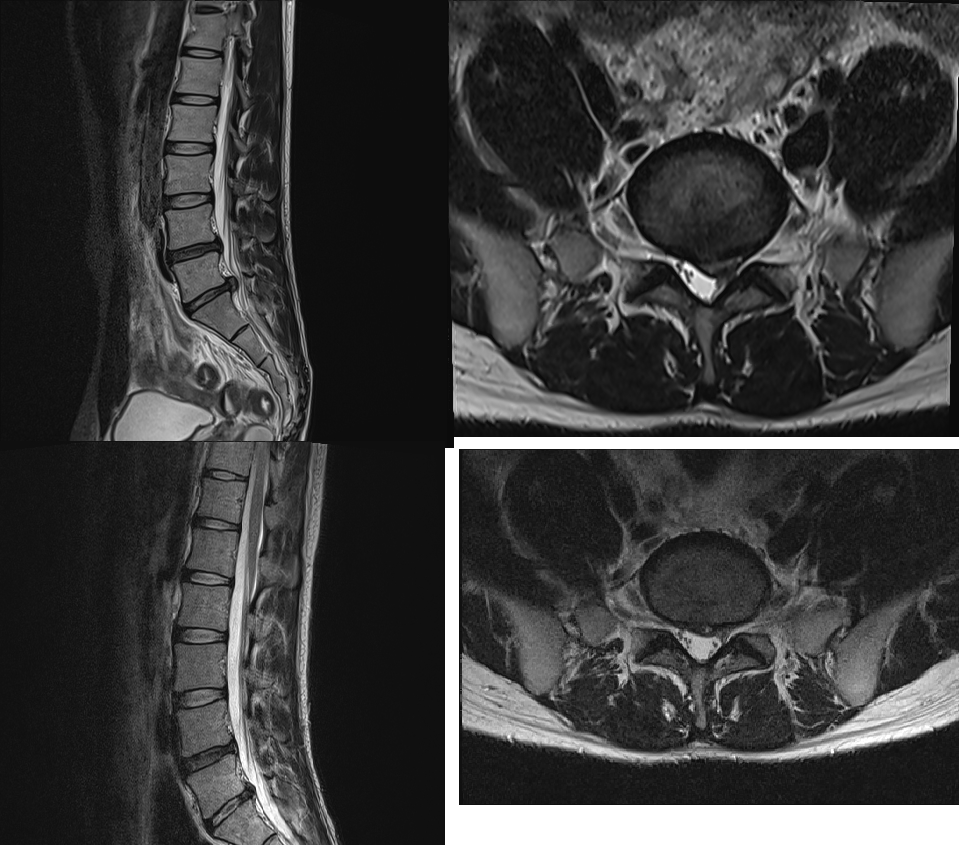

위 사진 두장이 작년 9월 통증이 너무 심해서 찍은 MRI이고

아래 사진 두장은 올해 4월 중순에 찍은 MRI 입니다. 디스크가 흡수된게 눈에 보이긴 하지만 통증이 계속 남아있습니다..

작년 말까진 걷기만해도 L5-S1 부위가 아팠는데 지금은 통증이 반정도 줄어서 걷는덴 문제가 없습니다.

현재 통증은 좌측 엉덩와 뒷꿈치 바깥쪽이 계속 저립니다. 자가로 하지직거상 검사를 했을때 다리를 들어올릴때 통증은 없습니다.. MRI 사진상으로 아직 탈출된 디스크가 있으니까 신경통이 있을수밖에 없는거겠죠?

• 일반적으로 영상의 소견과 증상의 정도가 일치하긴 하지만 꼭 그러한 것은 아닙니다. 올리신 사진의 소견으로 보았을 때 영상학적으로는 탈출된 디스크게 눈에 띄게 흡수되었고 많은 호전이 있는 것이 맞지만 주관적인 증상은 그보다 회복이 더딜 수 있습니다. 현재로서 질문자님께서는 지금 하고 계신 것처럼 최대한 코어 운동 등을 해주며 관리를 해주는 것이 최선입니다.

Spine MRI 로 보아서는 L4-5, L5-S1 에 Spinal cord 가 완전히 눌렸다가

호전된 것을 볼 수 있어 통증이 완전히 소실되는 것 보다는 남아 있을 가능성이

높아 어느 정도는 지속적으로 소염진통제를 드시는 것이 나을 수 있습니다.

MRI를 보면 디스크 탈출은 잘 호전되고 있는 상태입니다.